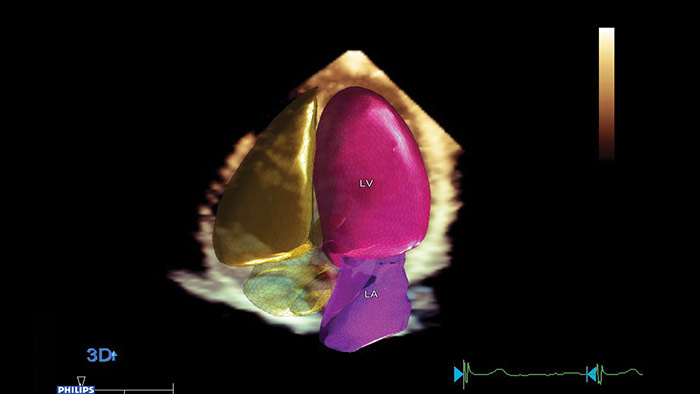

フィリップスのAnatomical Intelligence for Ultrasound(AIUS)は、高度な心臓のモデル化と実績のある定量化機能により、使いやすさ、高い再現性を実現。新しいレベルでの臨床情報の提供を可能にし、現代の医療現場が直面する経済的および臨床的課題に対応します。

AIUSは決まった手順を自動化し、ユーザーによる操作を最小限に抑えてコンピュータ主導解析を行う機能を備えています。臓器の構造を自動で認識し、解析を行うことでスクリーニング診断や計測の質を向上させ、心エコー検査をより迅速に、再現性高く実行することをサポートします。